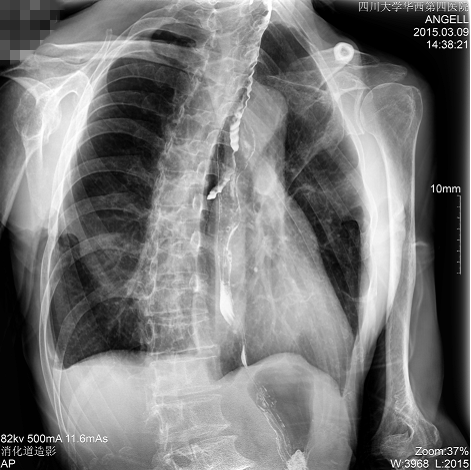

如下圖所示:該患者因吞咽時(shí)感到很難受,進(jìn)食時(shí)也經(jīng)常咳嗽故就醫(yī)診斷。華西醫(yī)院醫(yī)生使用動態(tài)DR為病人進(jìn)行消化道造影診斷,要求他吞鋇后發(fā)現(xiàn),食道各段通過順利,形態(tài)規(guī)則,雙側(cè)梨狀窩不對稱左側(cè)稍淺,多次吞咽動作后,仍見鋇劑滯留,并見鋇劑進(jìn)入氣管,屬于會厭征陽性。會厭功能紊亂,鋇劑進(jìn)入了氣管。

圖為斜位:通過動態(tài)影像可以清楚看到鋇劑進(jìn)入了支氣管道